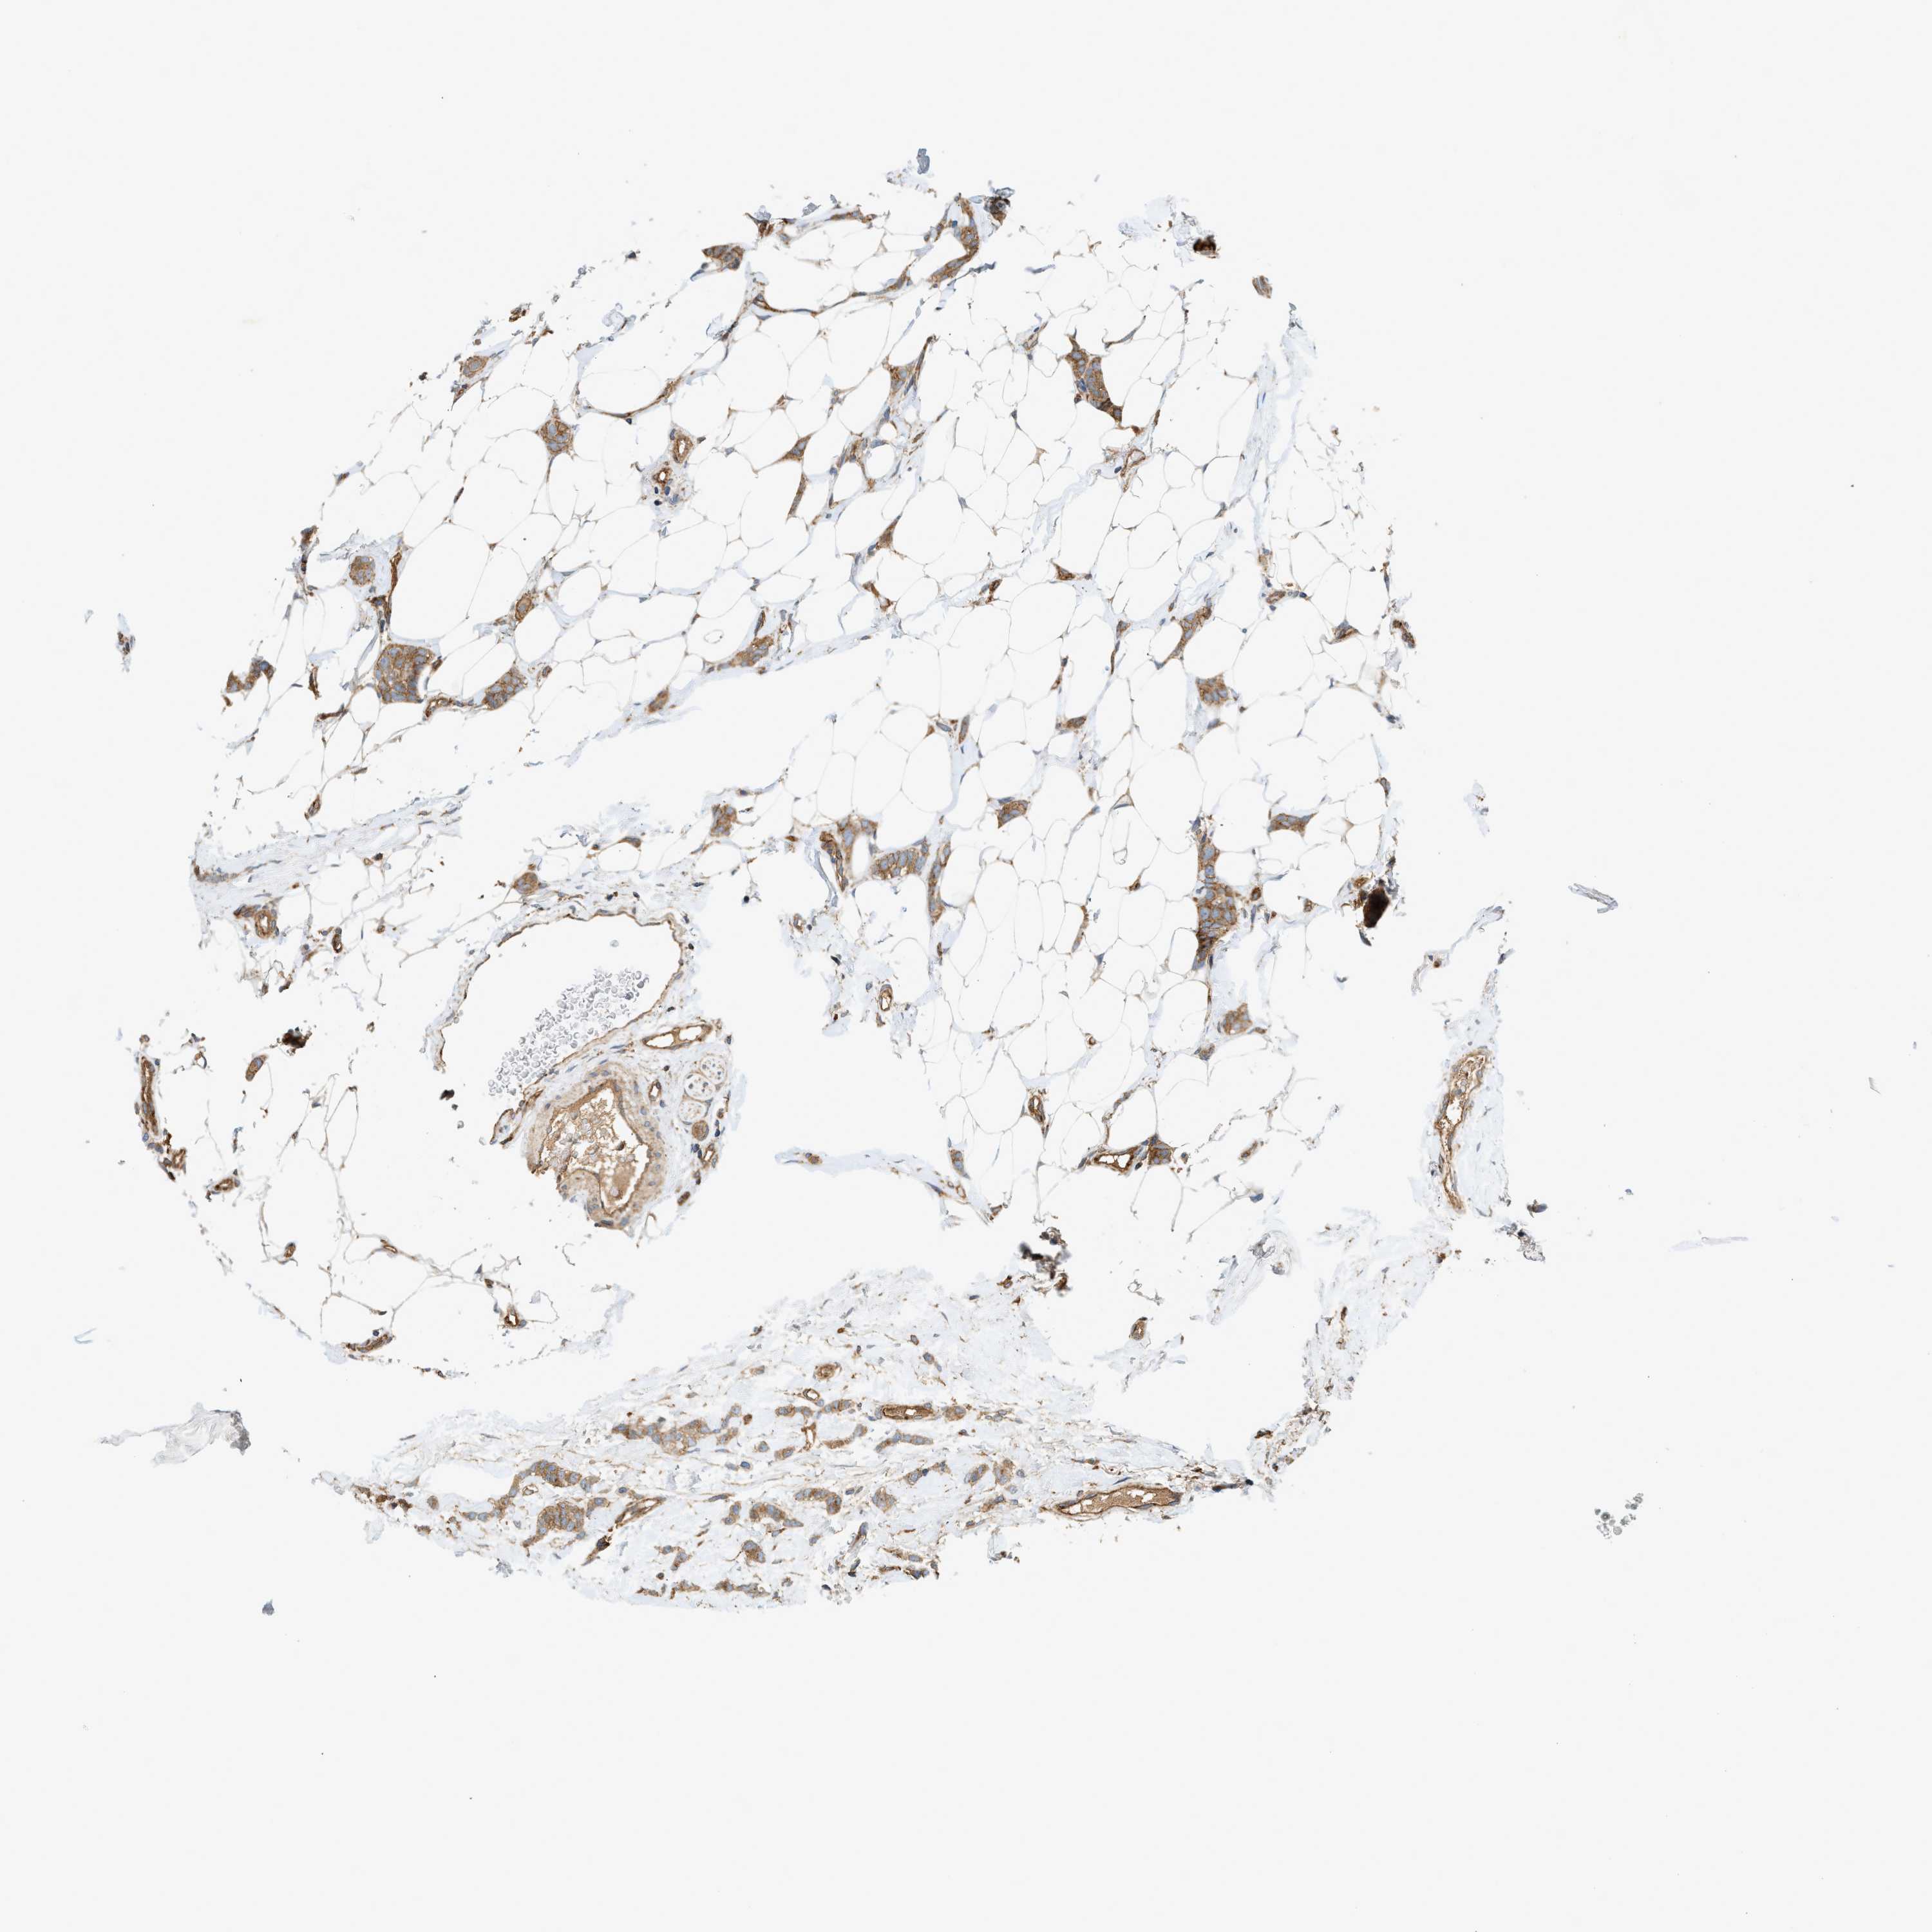

CANCER BREAST CANCER Show tissue menu

BRCA TCGA BRCA VALIDATION PROTEIN EXPRESSION